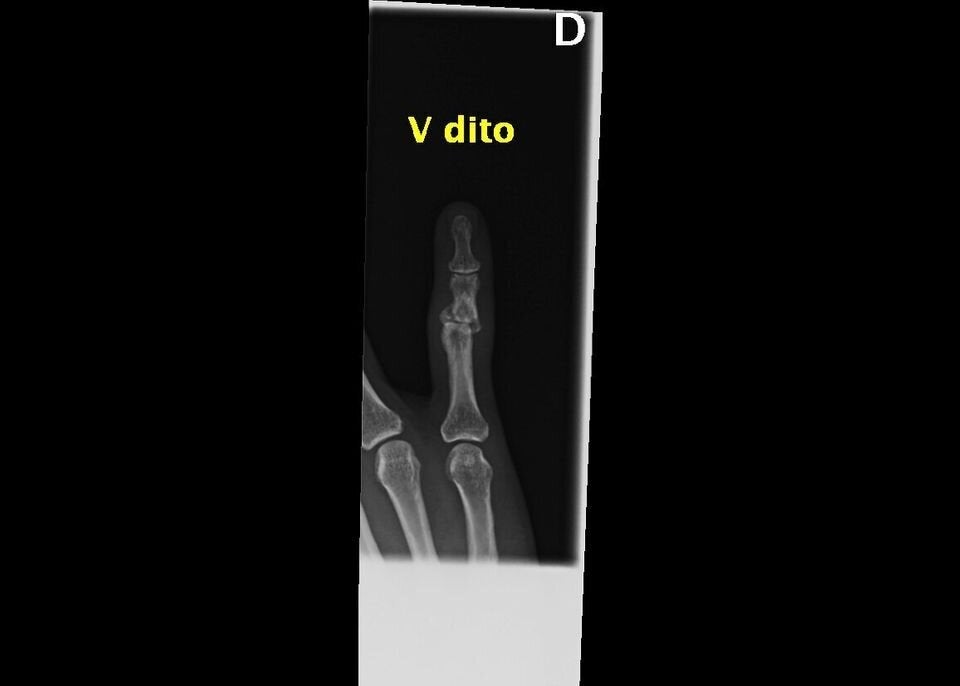

This isn’t the beginning of a novel, but the true story of a woman featured in “Invisibility Is Not A Superpower,” an exhibition that was set up in the atrium of the San Carlo Hospital in Milan, Italy, from Nov. 21 to Dec. 8. Through anonymous photographs and X-rays, the exhibition recounts the tragedy of women arriving at the emergency room and reporting that they have been victims of domestic violence.

“In this exhibition, a voice is given to the bodies and injuries of women who have suffered violence, weaving individual stories into a single narrative,” said photographer Marzia Bianchi. “The lives of the women differ, yet the pattern of violence is repeated, mainly at the hands of a partner, relative or acquaintance.”